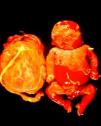

ClínicaLa infección sifilítica del feto produce, según nuestros datos y dependiendo de su severidad: aborto tardío espontáneo (20-40%), mortinato (20-25%), parto pretérmino (15-55%) con infección congénita o recién nacido vivo a término con infección congénita (40-70%). La infección congénita puede manifestarse, según su severidad, como muerte neonatal, como enfermedad neonatal o como infección latente, pudiendo desarrollar secuelas tardías. La muerte prenatal es el resultado más frecuente, pues ocurre entre el 40 y hasta el 70% de las gestaciones de mujeres con sífilis no tratada o tratada inadecuadamente; la mayoría de los recién nacidos vivos son asintomáticos, pero pueden desarrollar manifestaciones tardías15. Las manifestaciones clínicas pueden ser tempranas o tardías y su espectro es muy variado. La SC puede afectar a cualquier órgano del feto, más comúnmente hígado, riñones, médula, páncreas, bazo, pulmones, corazón y cerebro. De forma similar a la sífilis adquirida, la histología más característica de la SC es una endoarteritis obliterante, con infiltrado perivascular de linfocitos y células plasmáticas, acompañada de hiperplasia de la íntima de los vasos. Fibrosis y gomas se observan frecuentemente en esta enfermedad. En la placenta existe proliferación focal de las vellosidades con necrosis e infiltración focal de linfocitos maternos y células plasmáticas (fig. 2). Dichas vellosidades son inmaduras y están aumentadas de tamaño y amontonadas. El cordón umbilical también puede estar afectado, con la presencia de cambios inflamatorios y necróticos38. Existen estudios que apoyan la relación con la prematuridad, el bajo peso en el nacimiento y el pequeño tamaño para la edad gestacional; también con el aborto espontáneo, el cual puede ocurrir durante el segundo y principios del tercer trimestre39–42.